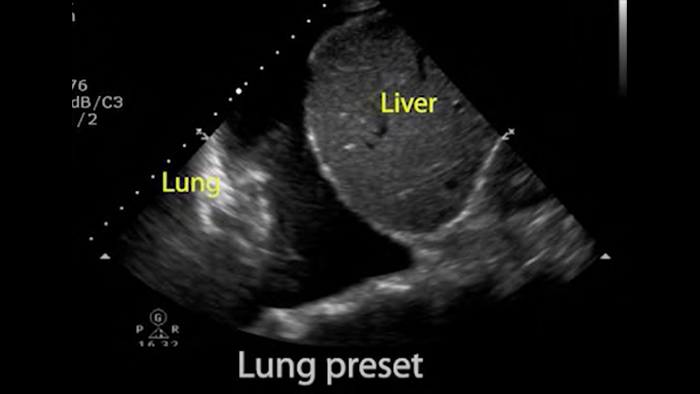

Gebruik Lumify voor luchtweg- en pulmonale beoordeling

De Lumify POCUS-oplossingen kunnen u helpen de endotracheale tube binnen de trachea te detecteren, ondersteuning te bieden bij urgente coniotomieprocedures, en diagnoses te stellen van pleurale effusie en interstitiële alveolaire ziekten.